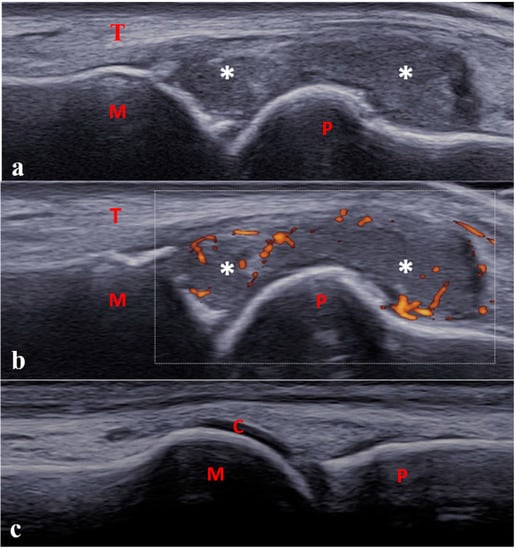

- Lanni, S.; Bovis, F.; Ravelli, A.; Viola, S.; Magnaguagno, F.; Pistorio, A.; Michele Magnano, G.; Martini, A.; Malattia, C. Delineating the Application of Ultrasound in Detecting Synovial Abnormalities of the Subtalar Joint in Juvenile Idiopathic Arthritis. Arthritis Care Res. 2016, 68, 1346–1353. [Google Scholar] [CrossRef] [PubMed]